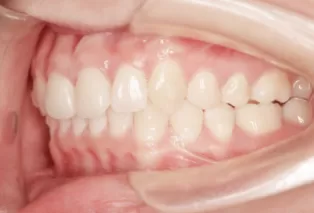

Intraoral photos